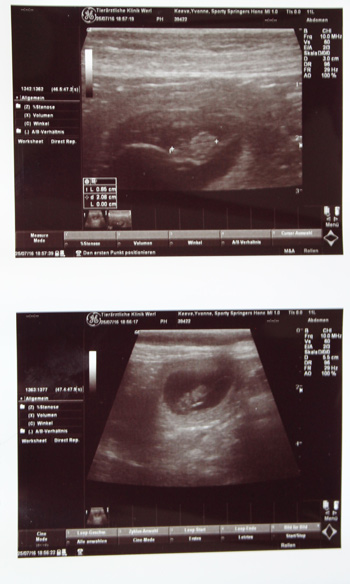

Die druckfrischen Bilder rechts zeigen die 8,5mm großen neuesten Familienmitglieder der Sporties Familie. Am letzten Augustwochenende können wir also tatsächlich die kleinen O-nneas begrüßen, während viele andere Familienmitglieder sich beim Workingtest tummeln.

Fame ist tragend nach Aron, was wir mit diesen Bildern bewiesen hätten. Jetzt muß nur noch weiterhin alles gut gehen.